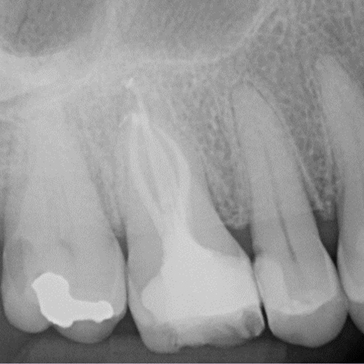

Case 4. Re-RCT of LR6